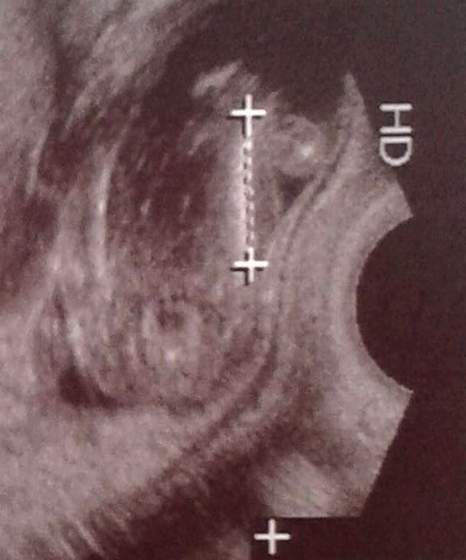

Dzięki za odpowiedź, choć ja już aż taka pewna nie jestem... Ten "siusiak" jest inny niż większość w necie, nie ma szerszego końca jak większosć z nich i w dodatku jest do kolan, wielki i gruby jak u dorosłego, a nie dziecka w połowie ciąży... Zastanawia mnie jeszcze to, że ten siusiak dziwnie w głębi ciała się zaczyna, a chyba powinien mieć początek od zarysu krocza, a nie jakby z brzucha? To widać na tych zdjęciach z widocznymi stopami. W dodatku ptaszek jest dziwnie w prawej pachwinie, a nie na środku krocza, co?

Najśmieszniejsze jest to, że wpatrując się w to zdjęcie zauważyłam obok drugie takie samo coś tyle, że mniejsze hehe Same zobaczcie, czy to nie wygląda jak odbicie lustrzane tego niby siusiaka?